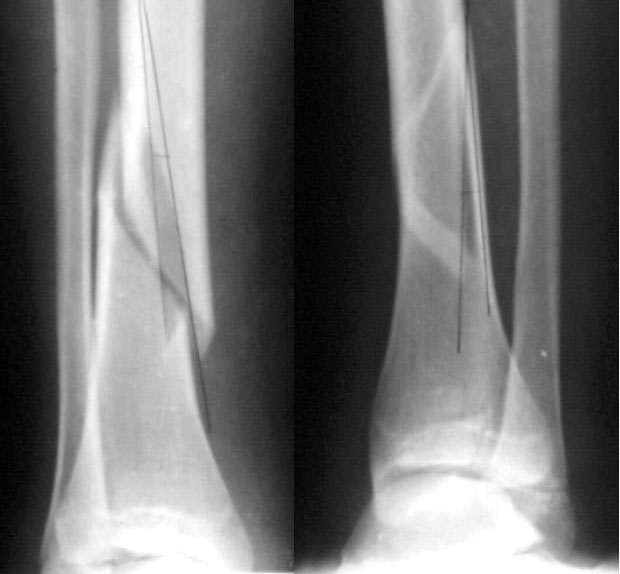

Девочка 14 лет полтора года назад оперирована в детской больнице по поводу спирального перелома костей голени (снимок 1)- выполнен закрытый остеосинтез стержнем Богданова, введенным ретроградно с медиальной стороны (снимок 2). Фиксатор после сращения удален

(см. снимки 3 и 4, после удаления, для сравнения со здоровой стороной, фас - стоя с нагрузкой на обе ноги). В настоящее время беспокоят боль и отеки в области голеностопного сустава при нагрузках, после ходьбы. В покое и ночью боли нет. Амплитуда движений в голеностопном суставе практически полная. Имеется заметная боковая нестабильность, т.е. несостоятельность дельтовидной связки и межберцоого синдесмоза. Складывается впечатление, что при остеосинтезе был отколот и смещен в сторону сустава костный фрагмент позади внутренней лодыжки, увеличилось смещение отломка заднего края, что привело к столь ранним проявлениям деформирующего артроза. Встает вопрос - что делать сейчас? Артодез - наверно, рано. Ревизию сустава, моделирующую резекцию? Пластику связок? Что-то еще? Заранее спасибо.